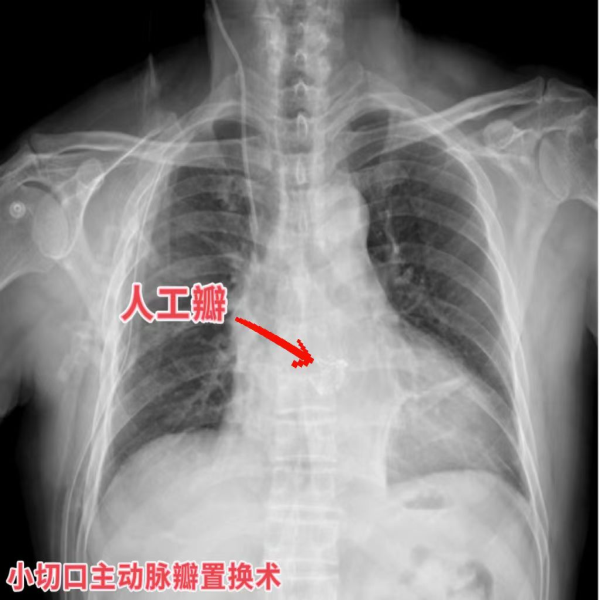

再说开篇时说的两位大爷,俩人在同一手术日先后接受了“小切口主动脉瓣置换术”和“胸腔镜二尖瓣成形术”。微小的切口缩短了手术时间,减少了手术创伤,使二老术后恢复迅速,很快回到了普通病房,术后恢复较快,很快康复出院。患者和家属对手术效果都非常的满意。

术后胸片(与常规正中切口对比):